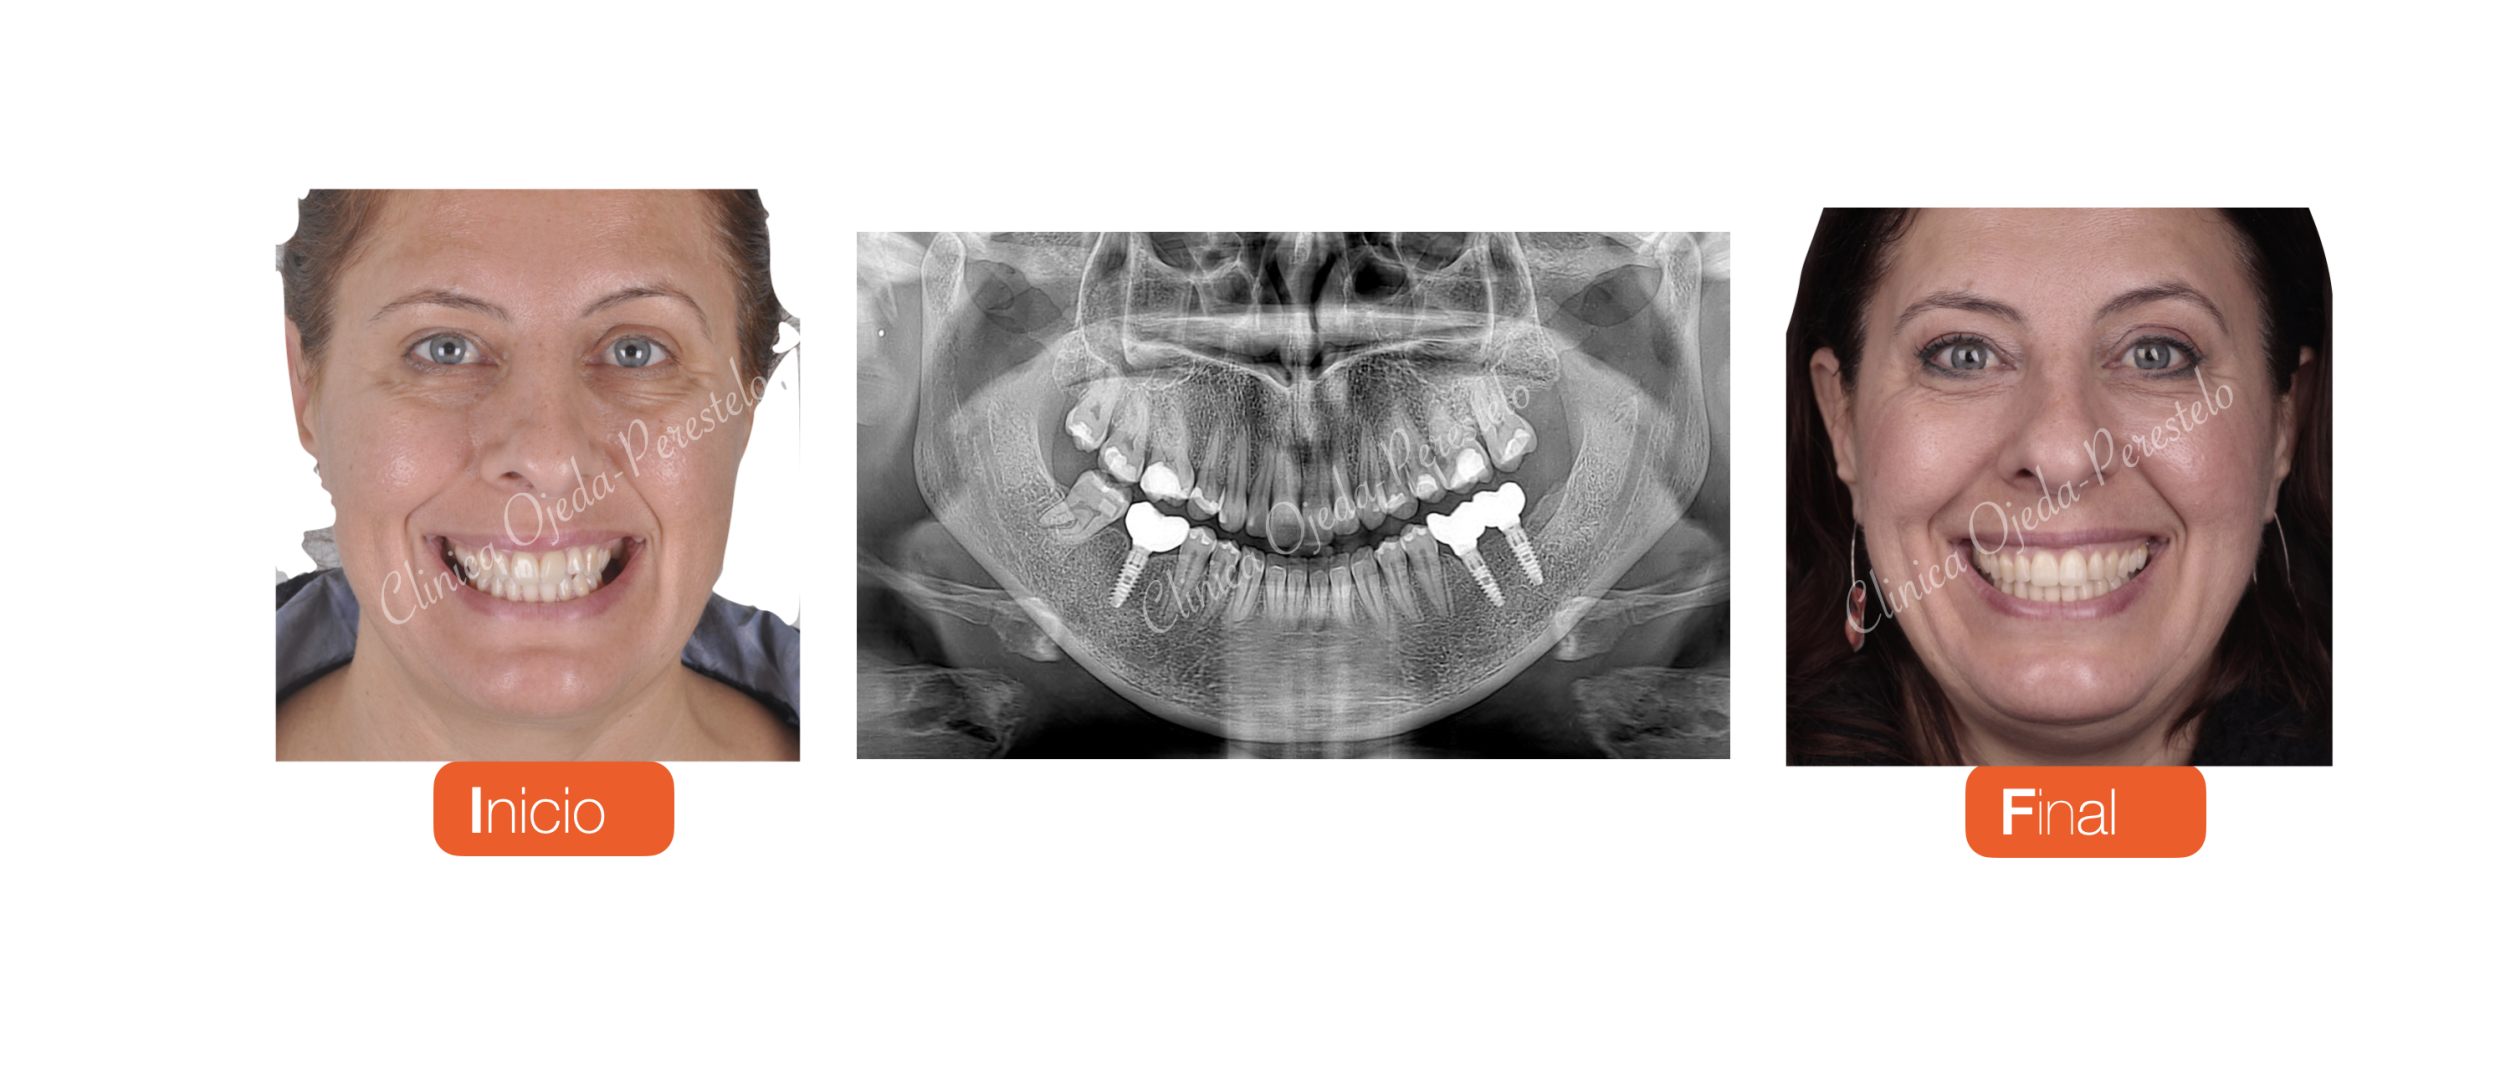

Queremos destacar la gran mejoría de la sonrisa acompañada de un correcto engranaje dentario en 4 series de  alineadores superiores e inferiores. En total sumaron 118 Maxilares y 99 Mandibulares que la paciente se cambiaba semanalmente. Una vez finalizada la fase ortodóncica la paciente procedió a colocarse sus implantes y coronas. Finalmente decidimos restaurar la pieza 22 a efectos de mimetizarla con la 12 a efectos de armonizar más su sonrisa.

A continuación realizamos la alineación y nivelación de las arcadas dentarias (Dr Ojeda-Perestelo) y adecuamos los espacios para la colocación de implantes en posición 46,36,37 (Dr Acorán Borges). Además se decidió dotarle a la pieza 22 (microdóntica) de una proporción similar a la pieza 12 con un microrelleno de la misma (Dra Trinidad Gandía)